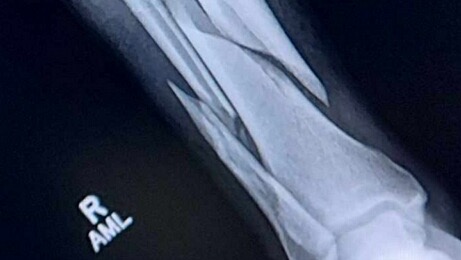

Hi, my name is Kori Savoie and I'm starting a fundraiser for my brother Evan. Evan was in a horrible dirt bike accident that left his right leg broken. It is a spiral fracture of both the Tibia and Fibula. We are grateful that he isn't in worse shape. However this accident has left him unable to work and to run his construction business. Evan will most likely be out of work, anywhere from four months to a full year for recovery. This comes of course at a horrible time. The holidays are approaching, medical bills are pilling up, as well as living expenses for him and his family. My brother is not one to ask for help, but it's really what he needs to keep his bills paid, his family in their home, and his business expenses covered until he can get back at it! He works extremely hard and I know he'd much rather be working right now than recovering from his injuries. Anything helps. I sure love my brother and want to help him get through this. The Savoie Family appreciates you all! Blessings and much love,